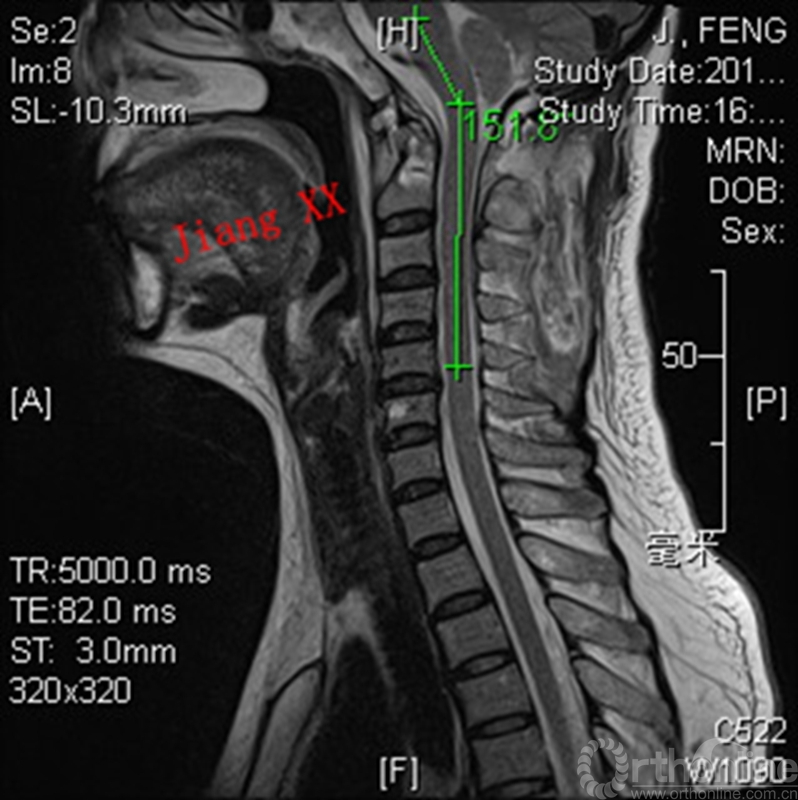

术前MRI

病例一:患者女性,49岁,因颈部活动受限4月入院,诊断为寰枢椎脱位,颅底凹陷。